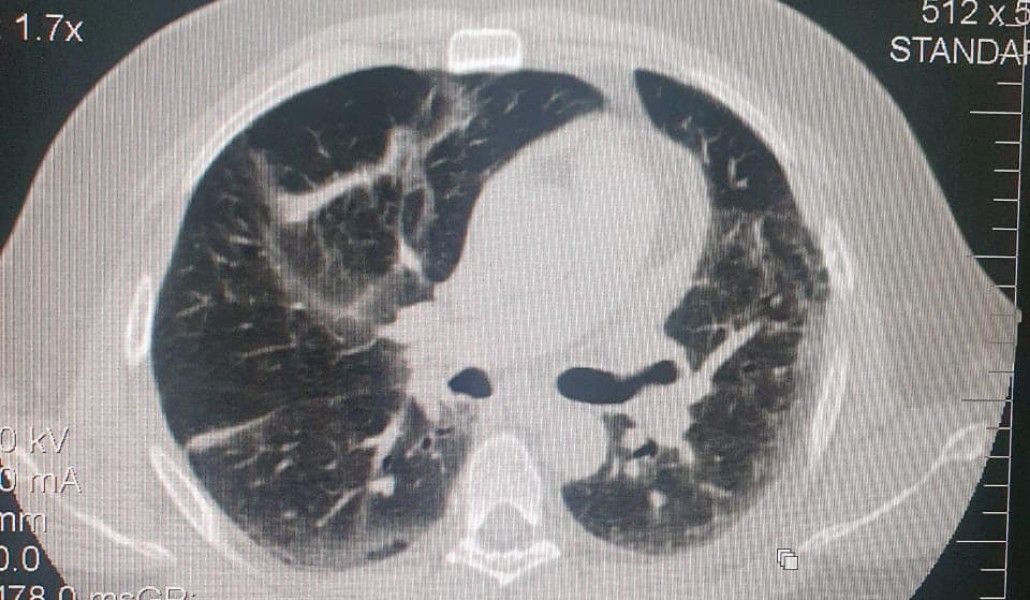

Երբ պատերազմի ընթացքում ինձ տեղեկացրեցին, որ ամերիկահայ բժիշկների կողմից մեզ է նվիրաբերվելու համակարգչային տոմոգրաֆիայի սարք, արագ որոշում ընդունեցի, որ այդ սարքի ամենամեծ պահանջարկը Կապանում է և որոշեցինք այն տեղադրել Կապանի բժշկական կենտրոնում։ Այսօր արդեն սյունեցիները կարող են համակարգչային տոմոգրաֆիա անցնել ոչ միայն Գորիսի, այլ նաև Կապանի բժշկական կենտրոնում։

Առաջին հետազոտություններն արդեն իրականացվել են։ Շուտով Կապանում ևս հնարավոր կլինի անցնել համակարգչային տոմոգրաֆիա նաև պետական պատվերի շրջանակներում՝ կառավարության կողմից սահմանված կարգով։